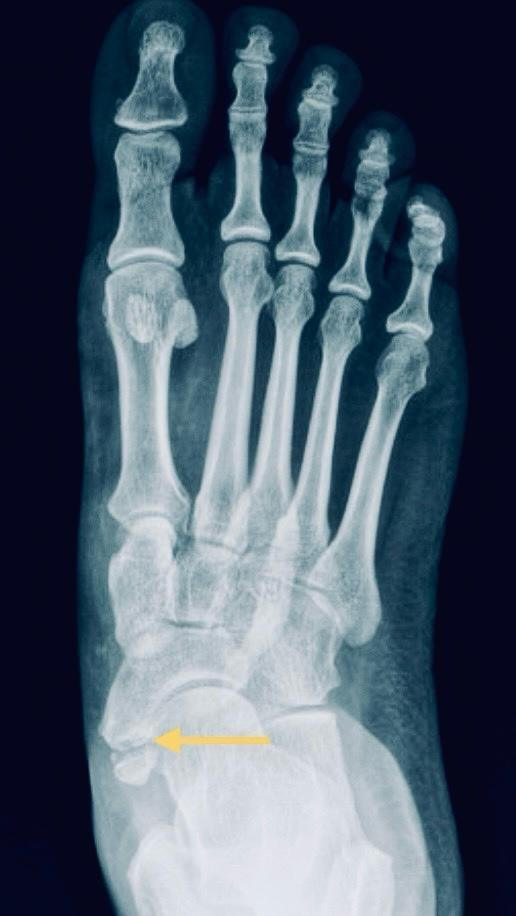

附生骨(Accessory bones)是骨骼結構的發育異常,成因是軟骨在骨化的過程中,並未與附近的骨骼主體合而為一,結果變成了獨立的小骨塊。雖然附生骨可以在骨骼的每個角落裡出現,但常見而可致痛的大都位於足部。其中由足部內側的舟狀骨衍生出來的附生骨:「副舟狀骨」,原來像蜥蜴般有保護色,隱藏在一至兩成人的足內,當中以女性為主,通常在青春期、骨骼成型前發病,惟大多數人都沒有明顯症狀。

負責將腳掌內翻和蹠屈,並維持足弓的脛後肌腱,本應連接在舟狀骨上,但卻變成與副舟狀骨結連,因此當年輕患者經常參與跑步和跳躍等運動時,脛後肌腱便會重複地拉扯副舟狀骨,逐漸產生肌腱和軟骨炎症,令足部內側腫脹和痛楚。若不及時治療,副舟狀骨日後或可併發出脛後肌腱炎,和功能障礙而導致扁平足。通常X光檢查已足夠為副舟狀骨斷診和分類,但磁力共振可用來排除其它病因。